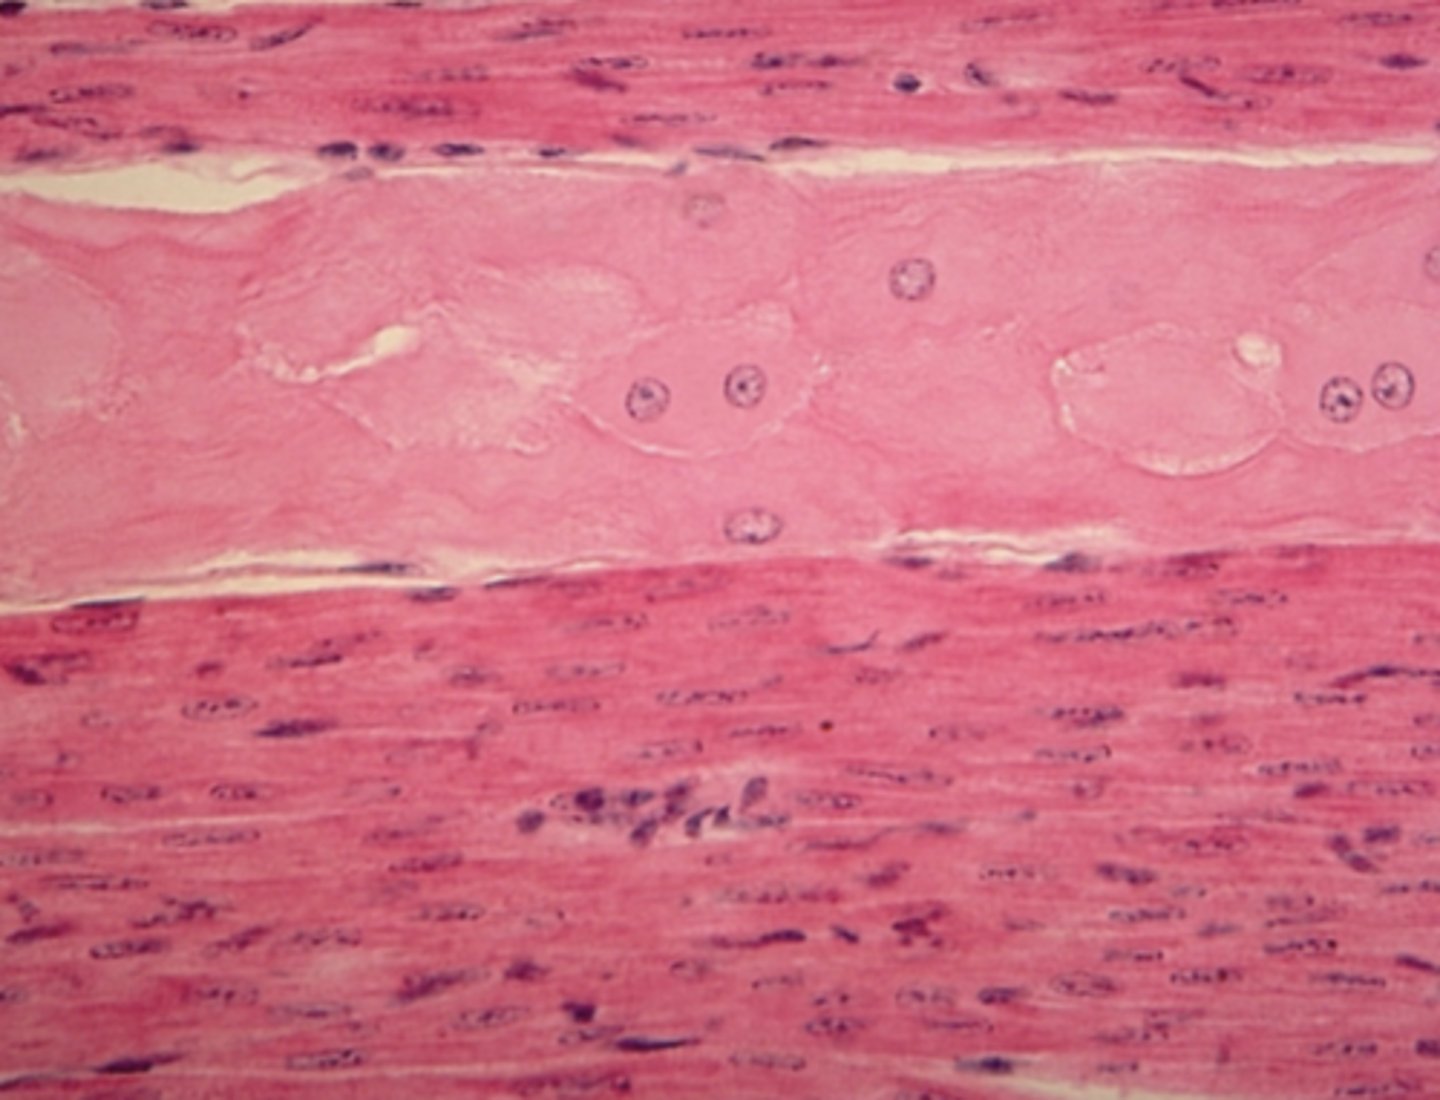

Muscle tissue

Which of the four major tissue types is presented in the following image of the heart:

Branched, striated cells with a central nucleus

Which is a feature of the tissue in the previous image of the heart (muscle tissue):

Tapered, non-striated cells with a central nucleusb. Branched, striated cells with a central nucleus

Branched, striated cells with a central nucleus

Long, striated cells with multiple peripheral nuclei

skeletal muscle

Which of the three muscle tissue types is presented in the following image:

cardiac

Which of the three muscle tissue types is presented in the following image: